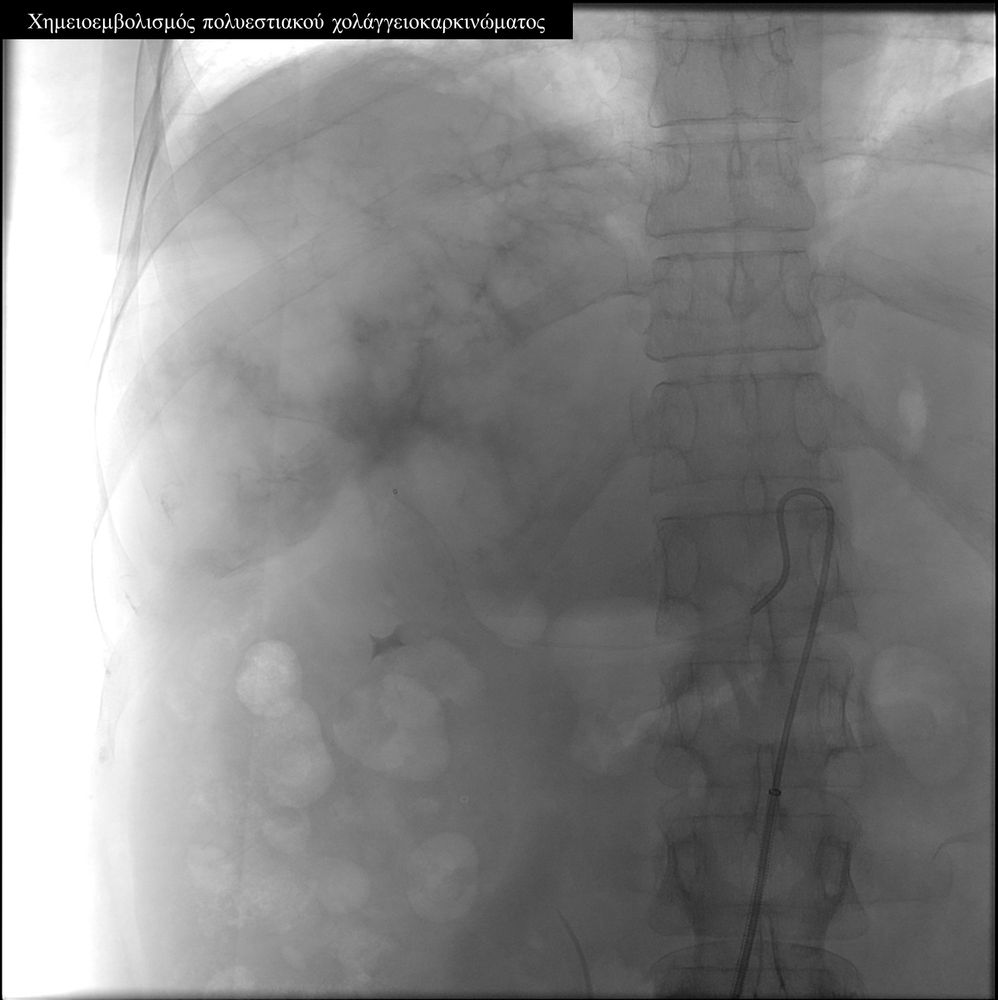

Ενδείξειςαποτελούν επίσης το χολαγγειοκαρκίνωμα και οι μεταστάσεις από καρκίνο του μαστού, καρκίνωμα νεφρού και σαρκώματα μαλακών μορίων.